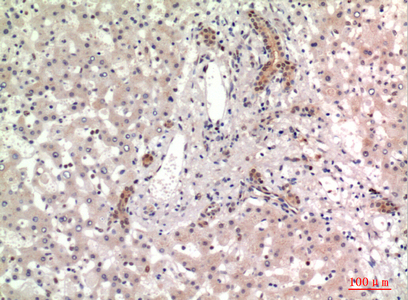

WB,IHC-P,IF-P,IF-F,ICC/IF,ELISA

WB 1:500-1:2000, IHC-P 1:100-1:300, ELISA 1:10000, IF-P/IF-F/ICC/IF 1:50-200